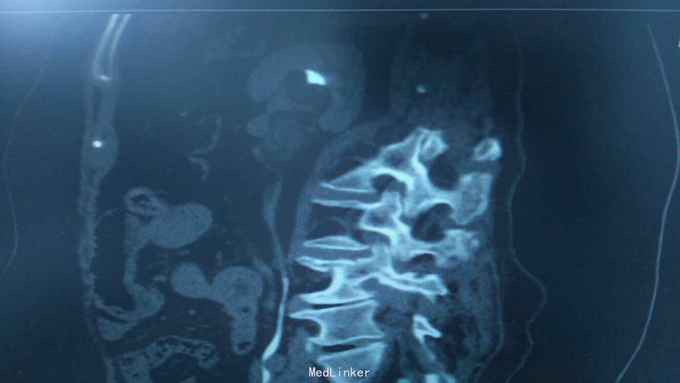

68岁,女性。 主诉:左侧腰痛1年,加重1个月。 病史:1年前无明显诱因出现左侧腰痛,无恶心呕吐,无肉眼血尿。1个月前加重,于外院查泌尿系彩超显示:左肾积液,输尿管显示不清。

诊断:双肾盂旁囊肿 治疗:因患者肾盂未明显受压,疼痛症状不明显,等待观察,暂未予处理。

双侧同时出现的病例并不多见,临床只能通过泌尿系统CTU或增强CT加以鉴别,彩超无法区分肾盂积水及盂旁囊肿。